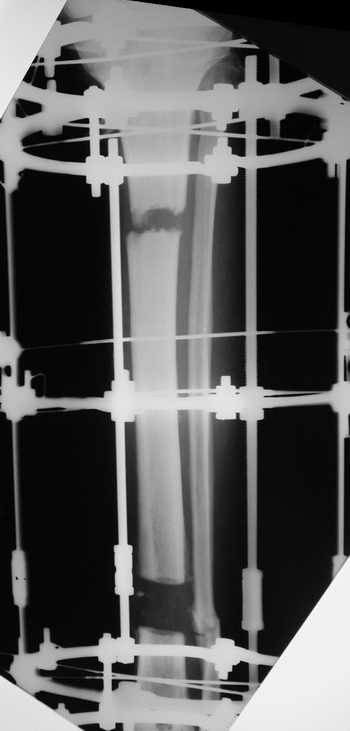

Мужчина, 33 года, резекция б\б кости по поводу остеомиелита после открытого перелома. Стандартная методика билокального остеосинтеза (рис 1 и 2). В конце удлинения выявилось неудовлетворительное взиморасположение перемещенного фрагмента и дистального отломка (рис 3). Планирование (рис 4).

Адаптация отломков гексаподом за 5 дней (рис 5). Замена гексапода на обычные штанги (рис 6 и 7)